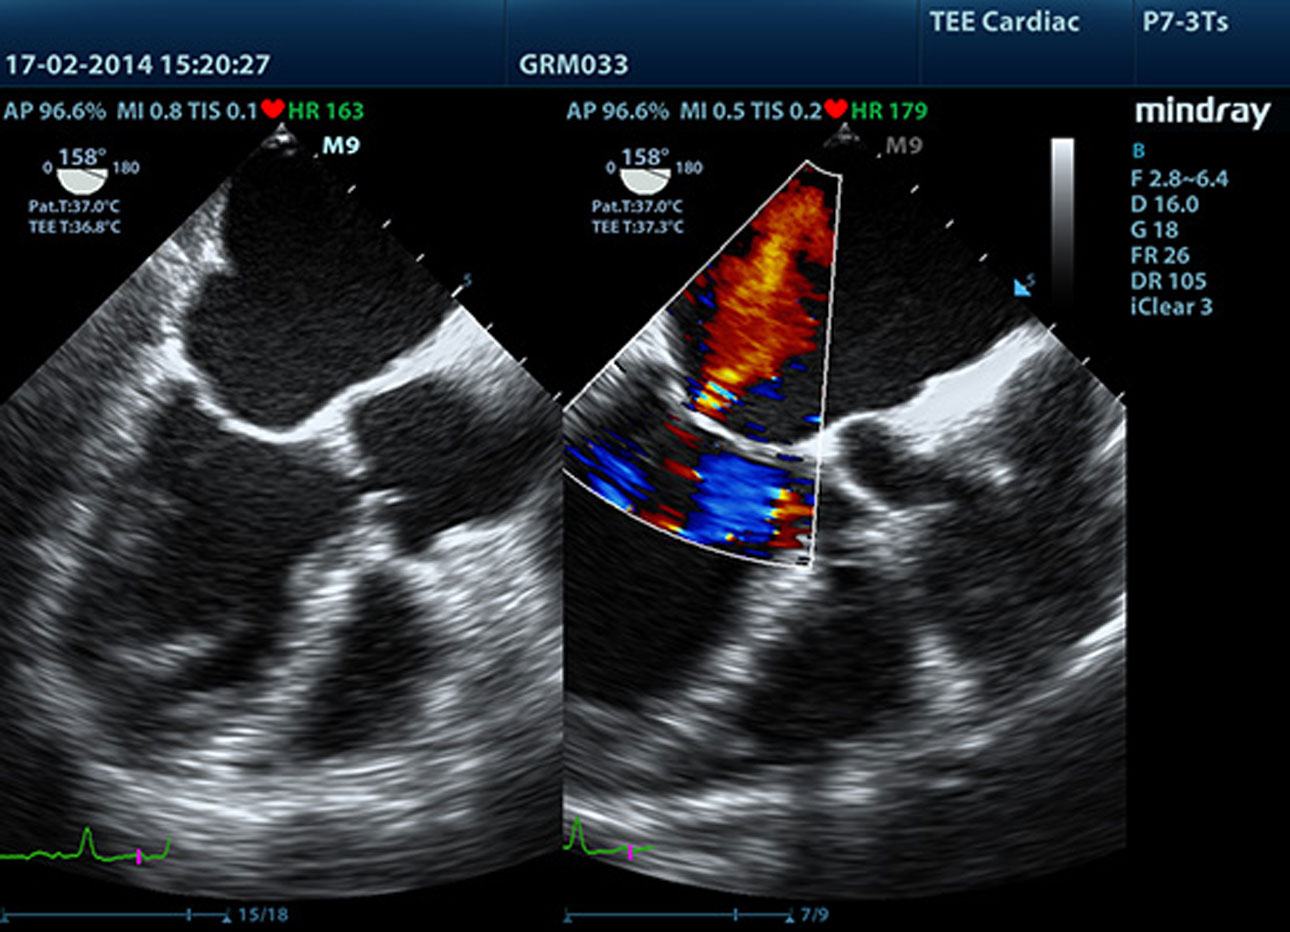

Ecocardiografía de estrés

Obtenga mediciones exactas de la función miocárdica en respuesta a un estrés externo o fármaco.